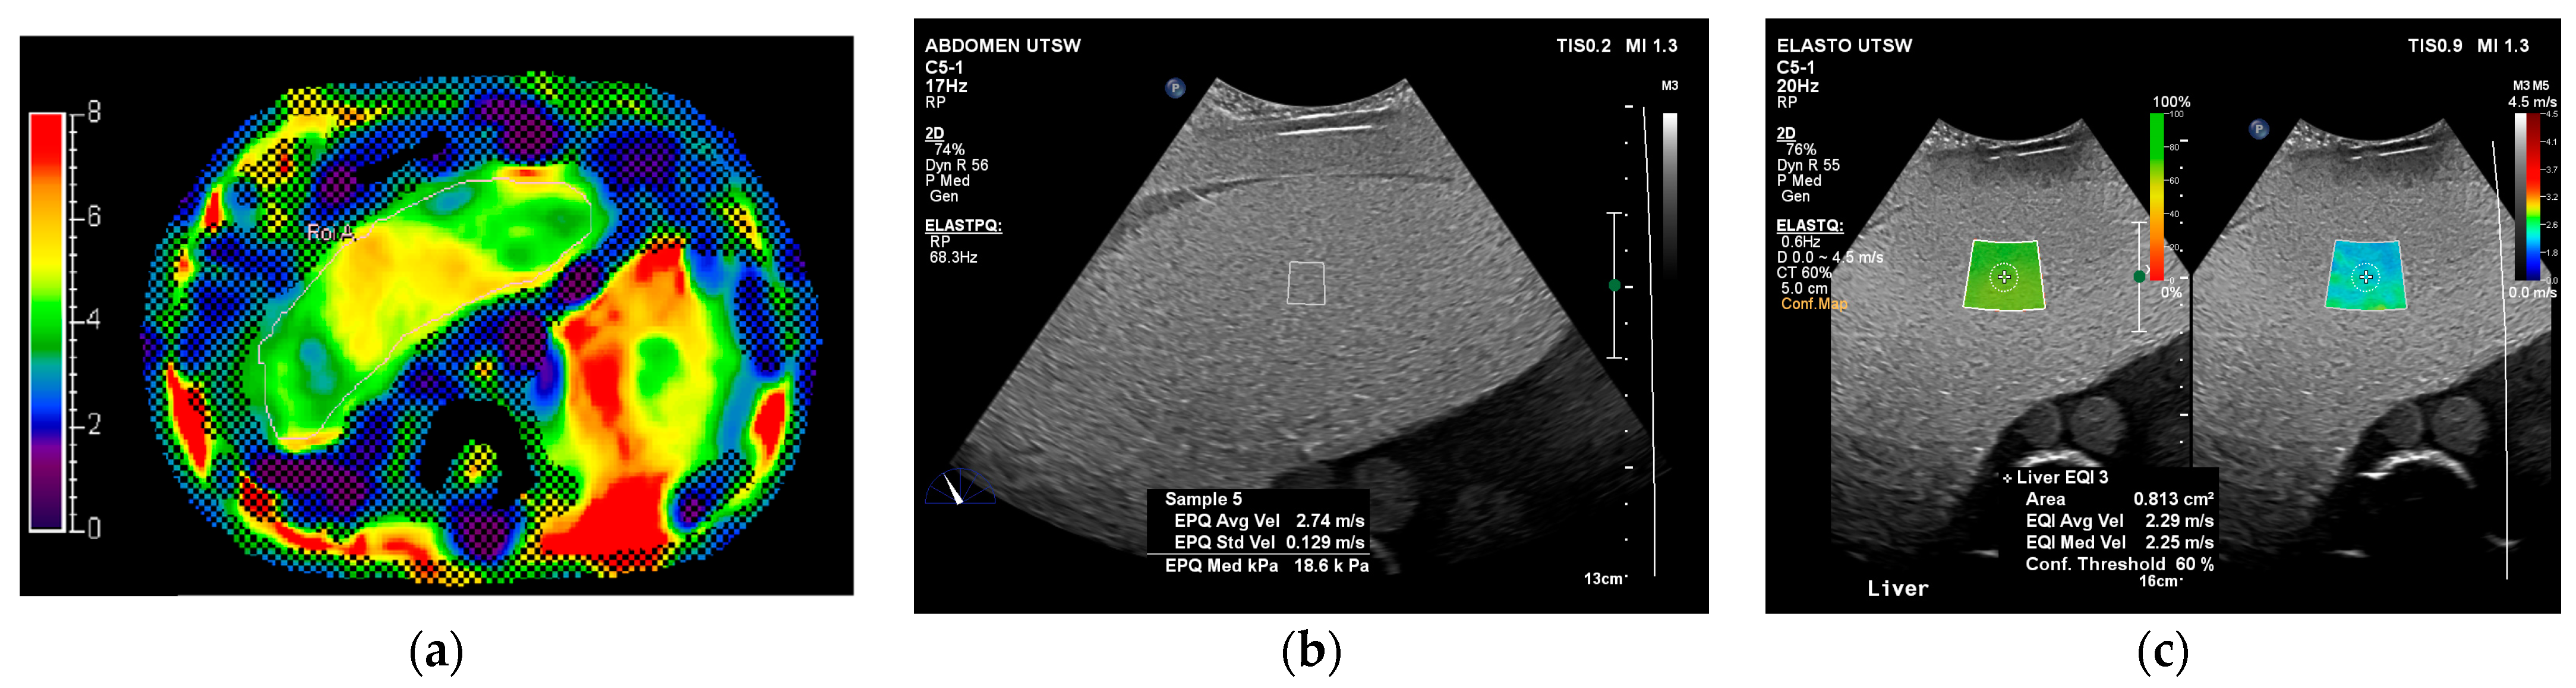

| Equipment (Model) | Software Version | Probe | Acquisition | Anthropomorphic Abdominal Phantom | Shear Wave Liver Phantoms |

|---|---|---|---|---|---|

| GE (Logiq E10) | R3 | C1-6 | 2D shear wave | x | x |

| Philips (Epic 5G) | 9.0 | C5-1 | Point and 2D shear wave | x | x |

| Siemens (Sequoia) | VA40A | 5C1 | Point and 2D shear wave | x | x |

| Philips 1.5 T (Ingenia MRE) | 5.1.7.3 | x |